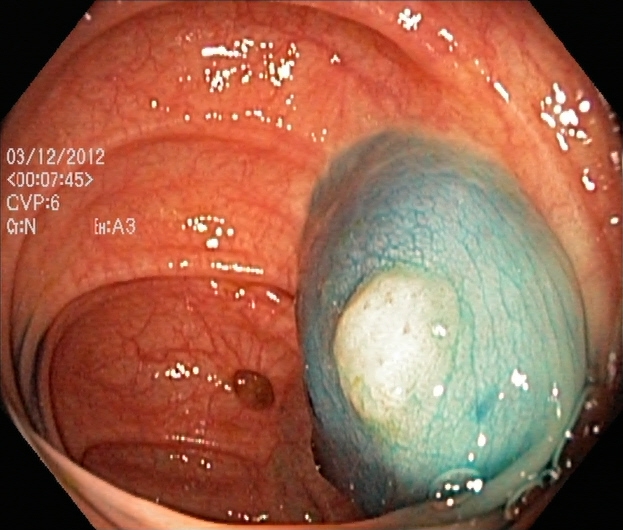

An automatic and efficient Computer-Aided Diagnosis (CAD) system in a clinic could assist medical experts during the endoscopic and colonoscopy procedure to improve the detection rate by finding unrecognized lesions and act as a second observer by providing better insights to the gastroenterologist concerning the presence and types of lesions. With this inspiration, we conducted five experiments to classify 161616 classes of GI tract conditions for the Medico Multimedia Task at MediaEval 2018 (Pogorelov et al., 2018b). One example for each of the 16 classes is depicted in Figure 1.

Figure 1. Sample images of GI findings. Each image represents one of the 16 classes from the dataset used for the Medico 2018 challenge (Pogorelov et al., 2017c, a).